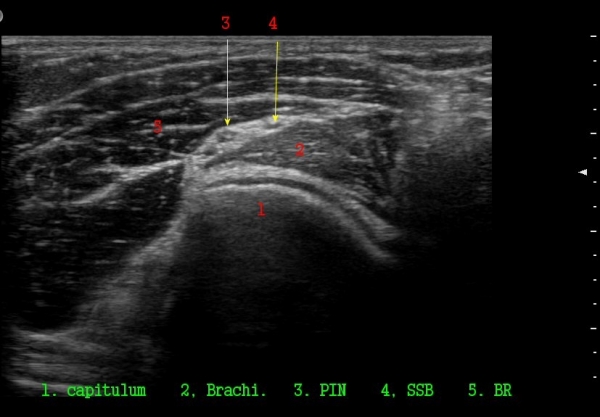

ŽÃËÀÚ¸¦ ¸»´ÜÀ¸·Î À̵¿ÇÏ´Ï ¿ä°ñµÎ ºÎÀ§¿¡¼­ Àú¿¡ÄÚ ³¶Á¾ÀÌ Èİñ°£½Å°æºÐÁö¸¦ Ç¥ÃþÀ¸·Î

ÀüÀ§½Ã۰í ÀÖ´Ù(±×¸² 2, 3,)